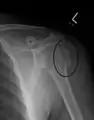

A fracture of the greater tuberosity as seen on AP X ray

A fracture of the greater tuberosity of the humerus